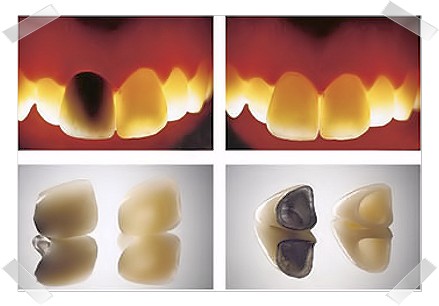

Press-keramika (bunlara "preslənmiş keramika, presləmə qapaq, emaks, metalsız keramika, emax diş, litiyum disilikat, LiSi2, press farfor, Disilanyllithium, Lithium disilicate" da deyilir) əsasən ön dişlərin estetik bərpası üçün tətbiq olunan və xüsusi metalsız keramika materialından istifadə olunaraq hazırlanır diş bərpa növüdür. Hazırlanmasında məqsəd dişlərə mümkün olduğu qədər az zərər vermək və maksimal dərəcədə estetik nəticələr əldə etməkdir. Press-keramika qapaqlar dişlərin həm formasında, həm ölçülərində, həm də rəngində əhəmiyyətli deyişmələr etməyə imkan verirlər. Beləcə dişlərə ən az müdaxilə edilərək, yüksək səviyyəli estetik nəticəni əldə etmək mümkün olur.

Pressləmə keramika texnologiyası təbii dişlərə ən yaxın görüntü verə bilən çox möhkəm, yükgül və son dərəcə gigiyenik olan, yüksək dərəcədə kristallaşan Litium disilikat (LiSi2) keramikanın istənilən formada hazırlanmasına əsaslanır. Müxtəlif rənglərdə hazırlanan keramika blokları xüsusi fırınlarda əridilir və əvvəlcədən hazırlanan diş qapaqı formalarına yüksək təziq altında axıdılır. Bu formalarda kristallaşan keramika çox dəqiq və incə qapaqların (koronkaların) hazırlanması ilə nəticələnir.

Pressləmə keramika texnologiyası təbii dişlərə ən yaxın görüntü verə bilən çox möhkəm, yükgül və son dərəcə gigiyenik olan, yüksək dərəcədə kristallaşan Litium disilikat (LiSi2) keramikanın istənilən formada hazırlanmasına əsaslanır. Müxtəlif rənglərdə hazırlanan keramika blokları xüsusi fırınlarda əridilir və əvvəlcədən hazırlanan diş qapaqı formalarına yüksək təziq altında axıdılır. Bu formalarda kristallaşan keramika çox dəqiq və incə qapaqların (koronkaların) hazırlanması ilə nəticələnir.